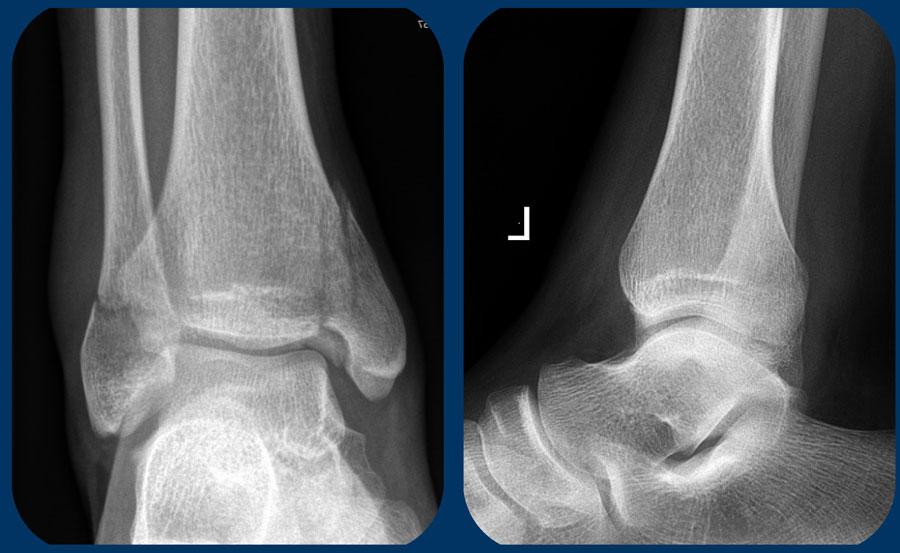

Trường hợp này phức tạp hơn.

Đường gãy xương mác nằm ở mức khớp chày mác xa (syndesmosis) và một số người có thể xếp loại đây là gãy Weber B, tuy nhiên hình ảnh không điển hình cho Weber B. Gãy Weber B có đường gãy chéo và nghiêng hơn do đây là gãy do lực đẩy, sẽ được thảo luận ở phần sau.

Chỉ cần quan sát hình ảnh, bạn có thể hiểu được cơ chế chấn thương (cuộn ảnh để xem).

Đây là gãy xương Weber A hai mắt cá giai đoạn 2, không ổn định.